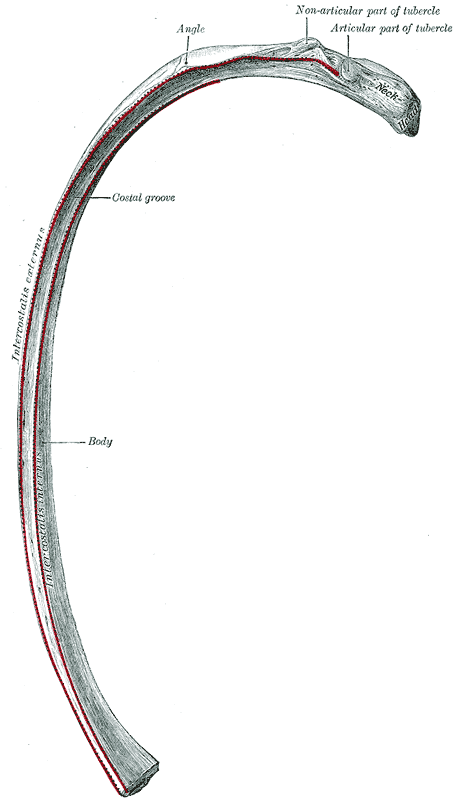

각 갈비뼈는 일반적으로 머리, 목, 몸통(체)으로 구성된다.

- '''머리''': 척추에 가장 가까운 부분으로, 갈비뼈 머리의 관절을 통해 척추와 연결된다. 머리에는 일반적으로 두 개의 관절면이 있는데, 위쪽 관절면은 바로 위 척추뼈의 아래쪽 관절면과, 아래쪽(더 큰) 관절면은 같은 번호 척추뼈의 위쪽 관절면과 연결된다. 또한, 척추뼈의 가로 돌기는 같은 번호 갈비뼈의 결절과도 연결된다. 두 관절면 사이의 능선에는 갈비뼈 머리 내 인대가 붙는다.[5]

- '''목''': 머리에서 가쪽(바깥쪽)으로 뻗어 나가는 납작한 부분으로, 길이는 약 3cm이다. 앞면은 매끄럽고 뒷면은 거칠며 여러 구멍이 있어 인대가 부착된다. 위쪽 가장자리에는 앞쪽 갈비 가로 인대가 붙는 능선이 있고, 아래쪽 가장자리는 둥글다.

- '''결절''': 목 뒷면에 있는 융기로, 관절 부분과 비관절 부분으로 나뉜다. 관절 부분은 척추뼈의 가로 돌기 끝 부분과 연결된다. 비관절 부분은 거칠며 결절 인대가 붙는다. 결절은 위쪽 갈비뼈일수록 더 뚜렷하다.

- '''몸통(체)''': 갈비뼈의 가장 길고 굽은 부분이다.

- '''각'''(갈비뼈각): 결절 앞쪽에서 갈비뼈가 아래쪽 및 가쪽으로 뚜렷하게 꺾이는 부분이다. 엉덩갈비근의 힘줄이 부착되는 지점이기도 하다. 이 지점에서 갈비뼈는 두 방향으로 휘어지고 축을 중심으로 약간 비틀린다. 각과 결절 사이의 거리는 2번 갈비뼈에서 10번 갈비뼈로 갈수록 점차 멀어진다. 이 사이 영역은 둥글고 거칠며 등세모근이 부착된다.

- '''늑골구''': 대부분 갈비뼈의 아래쪽 안쪽 면에 있는 고랑으로, 늑간 신경, 늑간 동맥, 늑간 정맥이 지나가며 보호받는 통로 역할을 한다.[6][4]